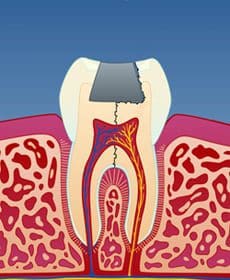

I tenner med store fyllinger er tannsubstansen rundt fyllingen svekket. Når man tygger, kan det etter hvert utvikles tynne sprekker i tannen. Disse sprekkene utvikler seg under fyllingen og forløper vanligvis på skrå bort fra tann-nerven (fig. 1). Infraksjonen kan imidlertid også gå inn til nerven (fig. 2) eller til og med dele tannen i to (fig. 3).